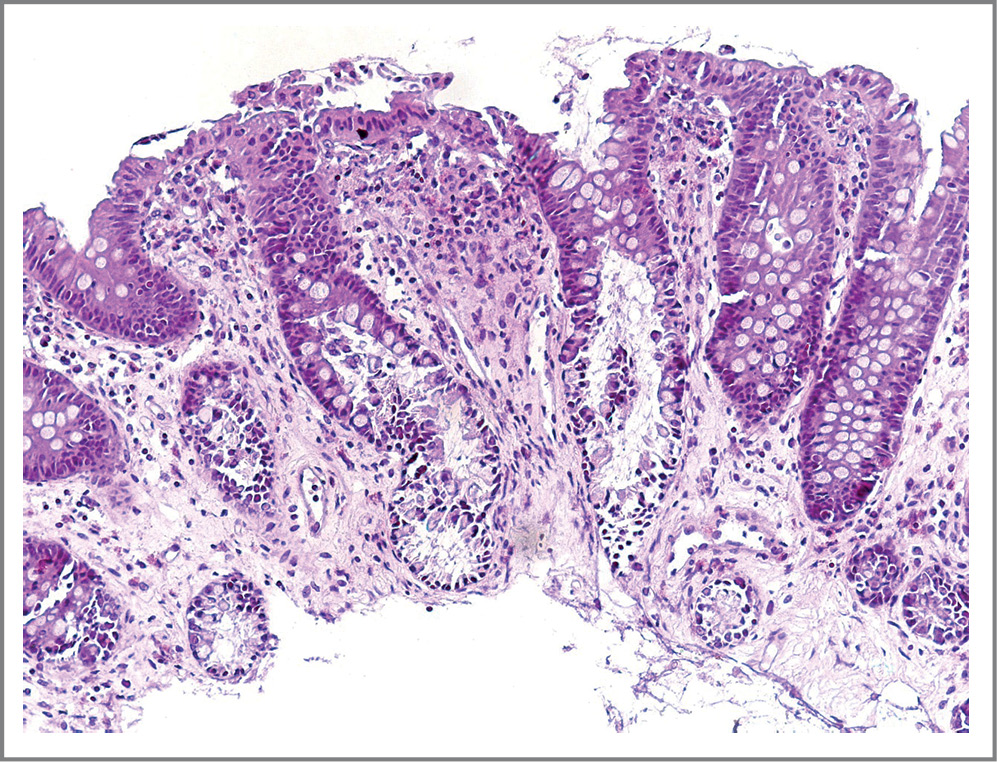

Дифференциальная диагностика острого колита инфекционной этиологии и болезни Крона (БК) гораздо сложнее. Salmonella и Yersinia в первую очередь поражают илеоцекальную область и аппендикс, тем самым имитируя БК. Подобно колиту Крона острый колит любой этиологии часто проявляется очаговым поражением слизистой оболочки толстой кишки. С другой стороны, колит Крона часто вызывает непоследовательные изменения архитектуры крипт, а гранулемы обычно отсутствуют (рис. 2).

Рис. 2. БК с поражением толстой кишки. Очаговые изменения архитектоники кишечных крипт и очаговый характер воспалительной инфильтрации с распространением клеток инфильтрата в подслизистый слой. Гранулемы в слизистой оболочке обычно отсутствуют. Окраска гематоксилином и эозином. ×120.

Fig. 2. Crohn’s colon disease. Focal changes in the archtectonics of the intestinal crypt and the focal character of inflammatory infiltration with the spread of infiltration cells into the submicular layer. Granules in the mucous membrane are usually absent. Coloration with hematoxylin and eosin. ×120.